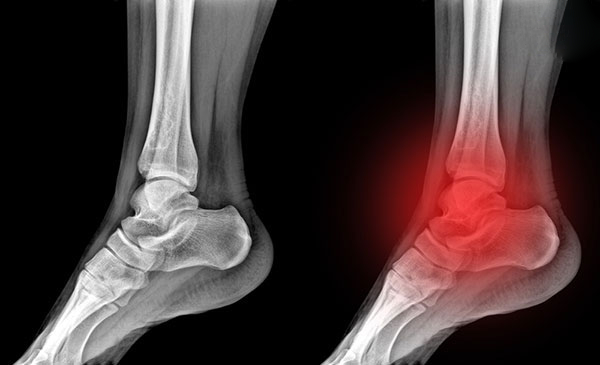

Thoái hóa khớp cổ chân

Thoái hóa khớp ở cổ chân là tình trạng tổn thương sụn và xương dưới sụn vùng cổ chân. Bệnh có thể xuất hiện ở mọi đối tượng nhưng thường gặp nhất ở những người trung niên, cao tuổi. Cơn đau làm khó chịu ở khu vực xung quanh mắt cá chân, dần dần tiến triển xấu hơn và làm hạn chế các chuyển động, đi lại khập khiễng, nặng hơn sẽ khiến cho người bệnh không thể tự đi lại mà phải nhờ sự hỗ trợ của người thân hoặc phải dùng xe lăn.

Hiện tượng thoái hóa khớp cổ chân

Hiện tượng thoái hóa khớp cổ chân phổ biến ở người trung niên, cao tuổi

Triệu chứng lâm sàng của khớp cổ chân được phát hiện qua các phương pháp chẩn đoán như: chụp X-quang, chụp cắt lớp vi tính (CT), siêu âm, chụp cộng hưởng từ (MRI)… giúp bước chẩn đoán chính xác cao hơn, từ đó hỗ trợ đắc lực cho các bước điều trị phục hồi tiếp sau đó.

Chụp X- quang

• Hình ảnh cổ chân qua chụp X-quang ghi nhận không gian khớp bị hẹp, sụn khớp bị mài mòn

• Xuất hiện gai xương nhỏ.